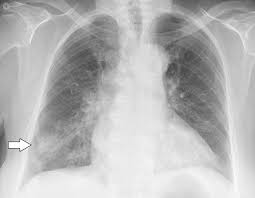

X rays are very helpful in the diagnosis of lung cancer in dogs. If you have lung cancer, it may be more difficult for your doctor to diagnose pneumonia. A white spot amidst the normal black lungs can therefore be a cancer, infection. Dog pneumonia or lung cancer. Pneumonia is a lung infection that leads to breathing difficulties and fluid in the lungs.

A definitive diagnosis of lung cancer requires a sample of tissue (biopsy). X rays are very helpful in the diagnosis of lung cancer in dogs. Primary lung cancer are frequently located in the caudal (towards the hind end of the pet) lung lobes, however can be located in any lung lobe and are usually a single mass in the lungs, unless the tumor has spread. If your dog has a chronic cough, you'll need to rule these out. The first of these possibilities could be investigated by bronchoscopy. A definitive diagnosis of lung cancer requires a sample of tissue (biopsy). The second kind of lung cancer in dogs is called metastatic lung cancer, which means the cancer originated somewhere else in the body, but has spread to the lung. Bacterial pneumonia is an inflammation of the lung usually caused by bacterial or viral infection but can be caused by inhalation of an irritant. The respiratory system consists of the large and small airways and the lungs. Lung cancer is actually the number one killer when it comes to cancers. But in some rare cases, it may be a lung cancer (primary or secondary). In both cases, you may have. Typical signs of bacterial pneumonia include fever, difficulty breathing, lethargy and coughing.

Primary lung cancer are frequently located in the caudal (towards the hind end of the pet) lung lobes, however can be located in any lung lobe and are usually a single mass in the lungs, unless the tumor has spread. My dog had pneumonia come on quickly this last august, we took her to the local er at 3am when we noticed her breathing labored and strange behavior. A white spot amidst the normal black lungs can therefore be a cancer, infection. Signs of the primary tumors in dogs. I haven't touched cigarettes a day in my life. Lung cancer often misdiagnosed as pneumonia urges requests for second medical opinions. Lung cancer is actually the number one killer when it comes to cancers. A definitive diagnosis of lung cancer requires a sample of tissue (biopsy). His appetite is basically normal though his blood work shows that he is anemic. 3 doctors agree send thanks to the doctor Other common respiratory diseases that might make you worried about cancer are …. Malignant tumors trigger inflammation in surrounding normal lung tissue, and they may obstruct. Pneumonia and lung cancer both affect the lungs but one is easily treatable and the other is potentially life threatening.

Deep Convolutional Neural Network With Transfer Learning For Detecting Pneumonia On Chest X Rays Springerlink from media.springernature.com Often, people with recurrent bouts of pneumonia tend to have unidentified lung cancer that can progress to advanced stages without appropriate treatment. A white spot amidst the normal black lungs can therefore be a cancer, infection. Here's why cancer can look like an infection: Persistent chest infections can be signs of something more serious than pneumonia, and unfortunately, it. A retrospective study of 1011 hospitalized patients with pneumonia was undertaken to assess the value of routine convalescent chest radiography for detection of underlying lung cancer. The first of these possibilities could be investigated by bronchoscopy. But the pneumonia density can obscure, or be distal to a cancer. Typical signs of bacterial pneumonia include fever, difficulty breathing, lethargy and coughing.

Bronchoscopy would also provide the opportunity to biopsy the lung and obtain mucous from the lung for. Other common respiratory diseases that might make you worried about cancer are …. As these can also be caused by other disease, diagnostics include a full physical exam, blood work, radiographs, and may also require bronchoscopy with. If you have lung cancer, it may be more difficult for your doctor to diagnose pneumonia. Lung cancer develops due to the overgrowth of. Lung cancer often misdiagnosed as pneumonia urges requests for second medical opinions. To investigate the mode of clinical onset of pulmonary carcinoma, 232 inpatients with this diagnosis were also stud … The respiratory system consists of the large and small airways and the lungs. A retrospective study of 1011 hospitalized patients with pneumonia was undertaken to assess the value of routine convalescent chest radiography for detection of underlying lung cancer. Pneumonia and lung cancer both affect the lungs but one is easily treatable and the other is potentially life threatening. Your veterinarian may recommend an fna and cytology or a biopsy, to confirm the diagnosis, and determine exactly what kind of lung cancer is present. Persistent chest infections can be signs of something more serious than pneumonia, and unfortunately, it. This is not to say the effects on a loved dog's body are the same as an infection.